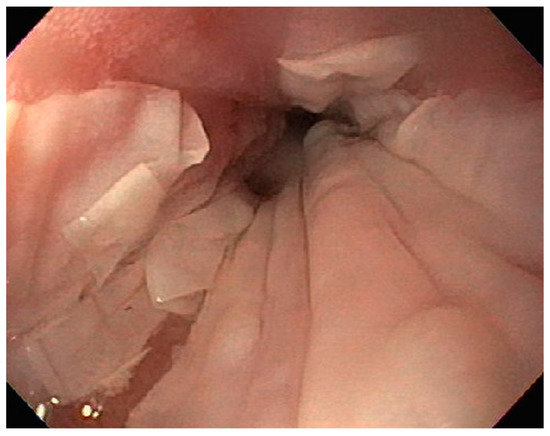

| 5 | M | 76 | Lung | Body | Cratered ulcers | Liver, bone and adrenals | Small cell carcinoma (poorly differentiated neuroendocrine Ca) | None | Death 7 days after EGD diagnosis of metastasis |

| 6 | M | 61 | Lymphoid | Unknown | Clean based ulcer | None | Marginal zone lymphoma | Rituximab, Zanubrutinib, umbrasilib. OCHOP regimen currently | Progressive disease per latest scans despite therapy |